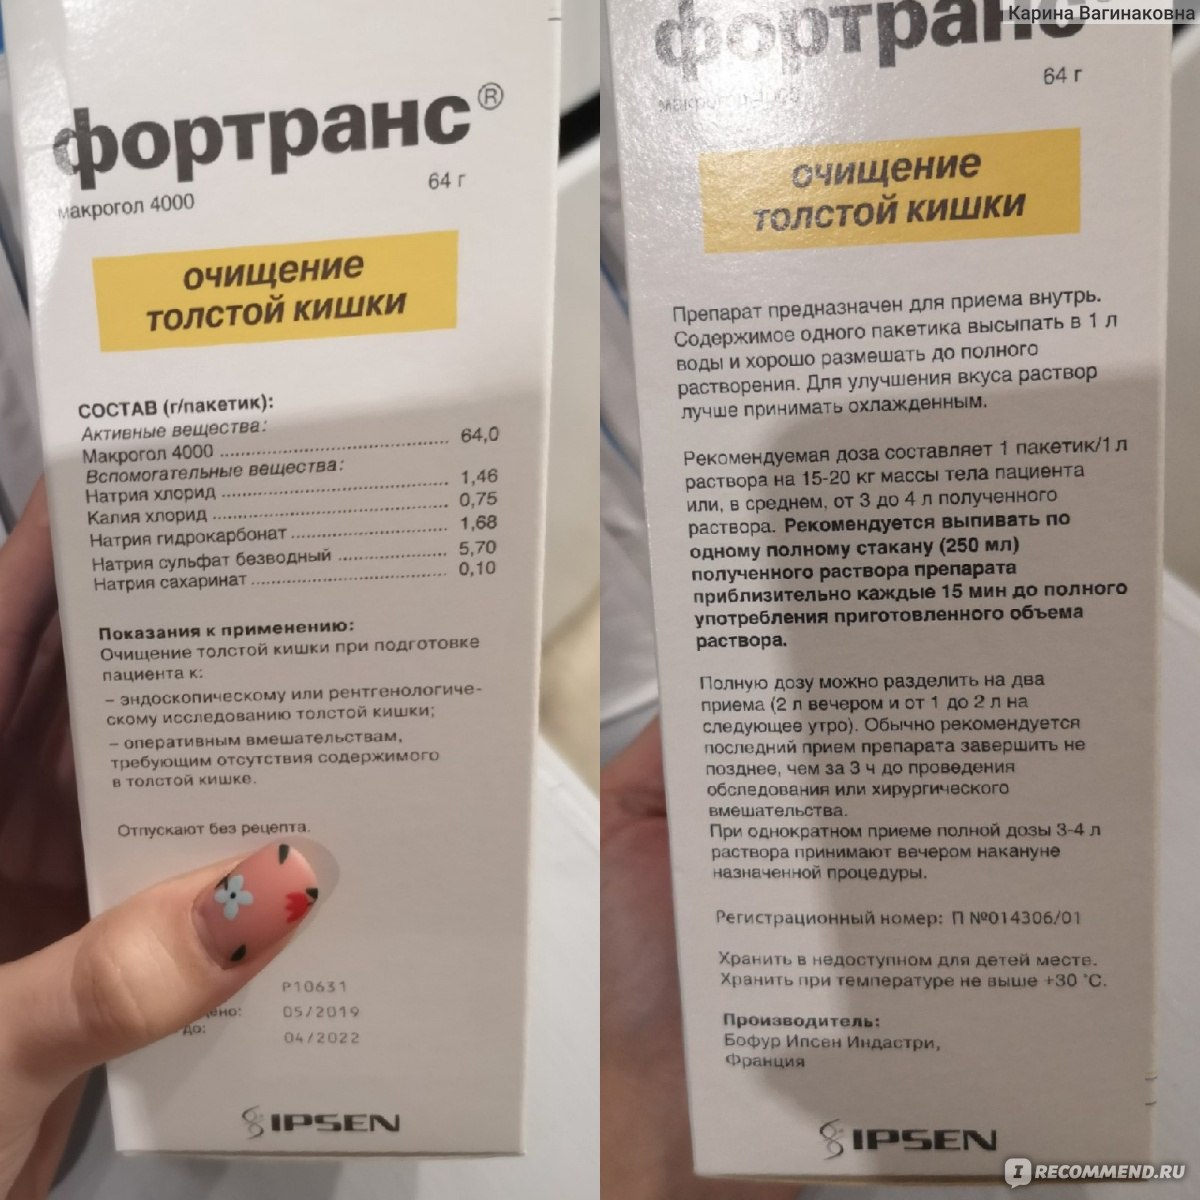

Подготовка к ирригоскопии: необходимые препараты